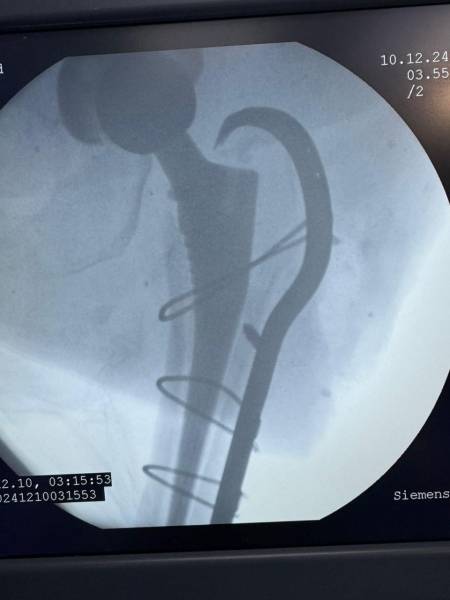

- إجراء عمليات جراحية معقدة و دقيقة في مجال العظام و المفاصل و الكسور و الإصابات ، رغم الضغط الكبير على المستشفى و أعداد المراجعين الكبيرة.

- تطبيق تقنيات جراحية حديثة و متقدمة، و ذلك في ظل التحديات التي يواجهها الفريق بسبب أعداد المرضى و المراجعين الكبيرة.